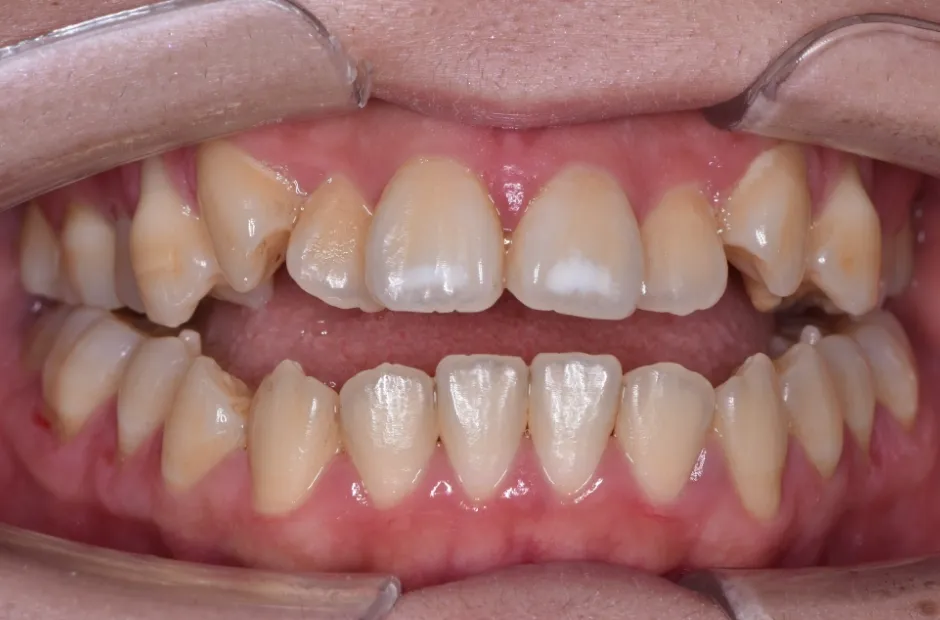

叢生

| 診断名・主訴 | 叢生 |

|---|---|

| 年齢・性別 | 43歳・女性 |

| 治療期間・回数 | 2年7か月 27回 |

| 治療に用いた主な装置 | 舌側矯正 |

| 抜歯部位 | 両顎4,4 |

| 治療費 | 100万円(税抜) |

| リスク・副作用 | 装置による違和感・疼痛・歯肉退縮・歯根吸収・虫歯のリスクなど |